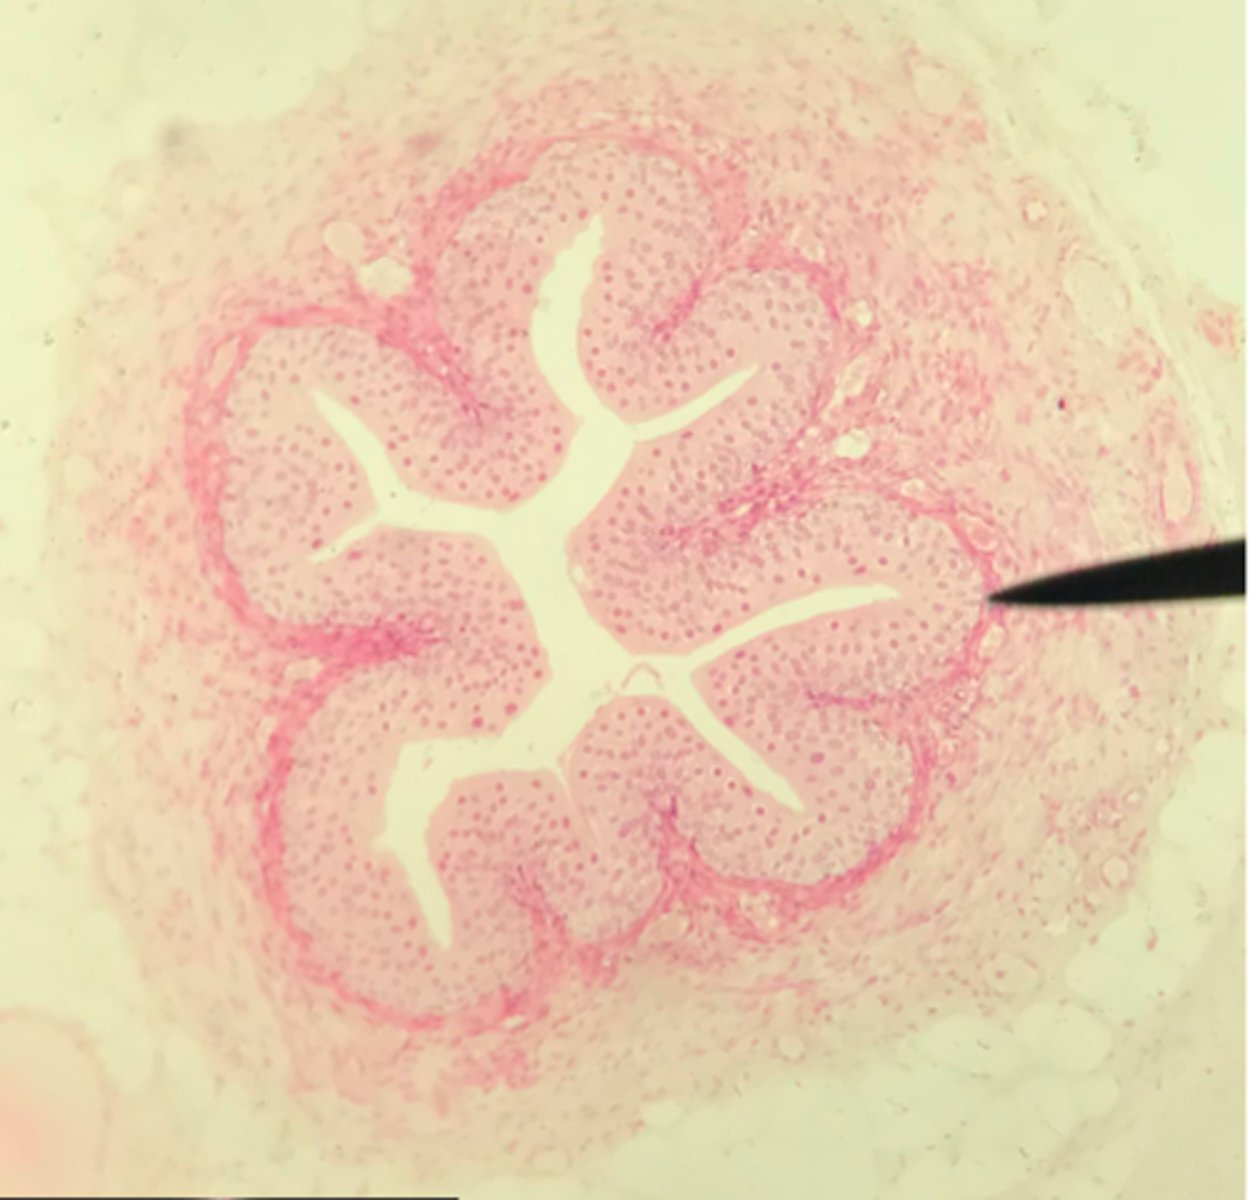

Cortex of the kidney

There are glomerular corpuscles present in the cortex. They are not present in the medulla

What layer of tissue of which organ is depicted on this slide? How can you tell?

Medulla of the kidney

There are no glomerular corpuscles present and there are numerous visible collecting ducts

What layer of tissue of which organ is depicted on this slide? How can you tell?

Glomerular (Bowman's) capsule (in the cortex)

What structure of the kidney is the blue arrow pointing at?

Collecting ducts (in the medulla)

What structure of the kidney are the blue arrows pointing at?

Glomerulus

What structure of the kidney is the pointer placed on?

Renal tubules (in the cortex)

What structure of the kidney is the blue arrow pointing at?